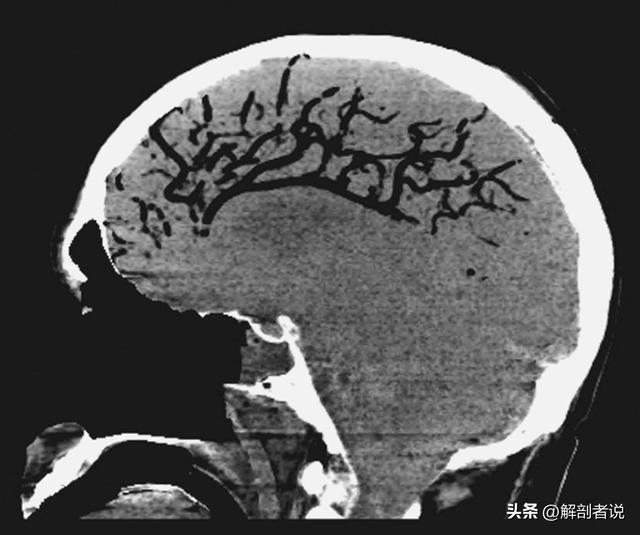

如果是少量泡沫血进入心腔,产生的泡沫血个头小,它们会随着血液循环,随机进入冠状动脉、肺脏、大脑等重要器官,到哪堵哪,分别造成心梗、肺栓塞、脑梗,不及时救治,也是非死即残(下图,少量泡沫血流进肺、脑等器官过程)。